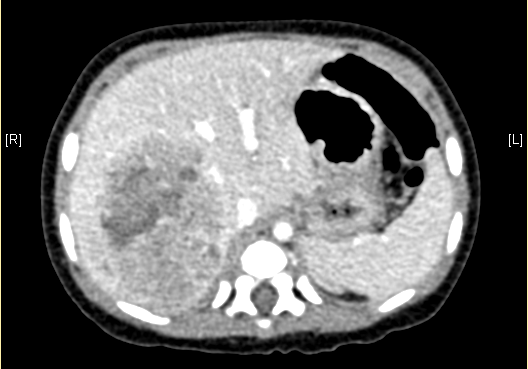

上腹部增强CT:肝右叶巨大占位,肝母细胞瘤可考虑。

术前CT检查:

动脉期